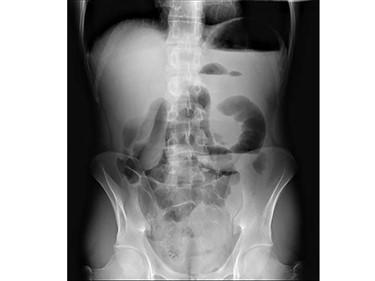

The abdomen had a tympanic percussion in the upper quadrants and tenderness in the epigastric area. He also presented with tachycardia, without other relevant findings. The laboratory studies revealed increased white blood cell count (WBC) and air-fluid levels on the abdominal x-ray (Fig. 1). Due to high suspicion of small bowel obstruction, an abdominal computed tomography was performed, revealing signs of an internal hernia of unknown type (Fig. 2).